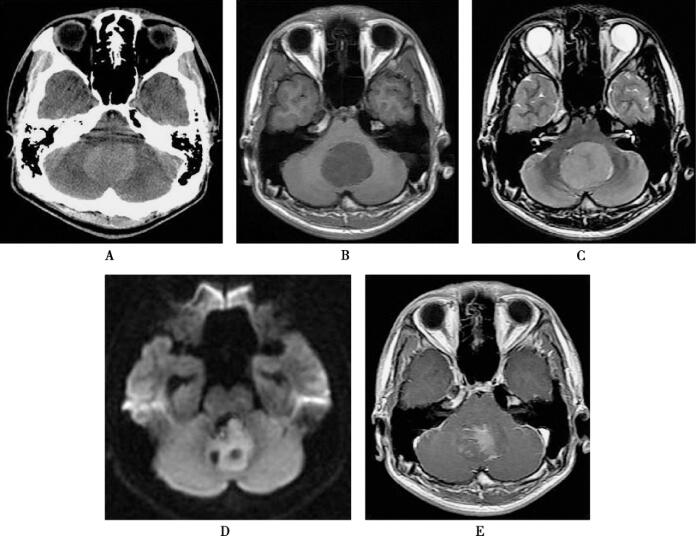

图1 髓母细胞瘤

头颅CT平扫显示后颅窝均匀高密度占位病灶,磁共振SE脉冲序列T1WI显示病灶位于小脑中部,呈均匀低信号,第Ⅳ脑室未显示;FSE的T2WI呈高信号,但其中心部信号稍低,DWI显示病灶信号较高,提示弥散受限,但内部有2个低信号斑点,增强扫描T1WI不均匀强化